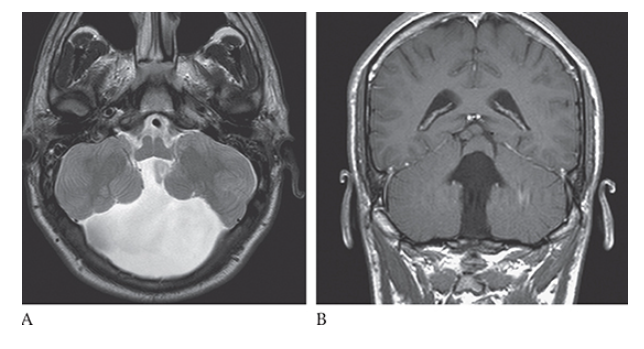

What is A

Dandy-Walker Syndrome. Axial T2W and coronal T1W

What is B

Dandy-Walker Syndrome. Axial T2W show absence of the cerebellar vermis.